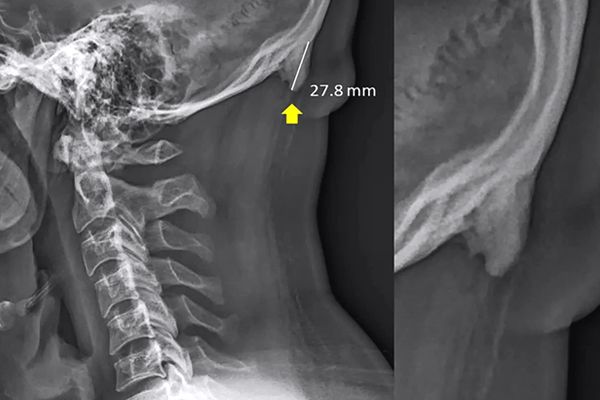

A recent report from BBC shows possible future impacts of technology on the human skeleton says that humans are growing a horn-like structure on their skulls because of excessive usage of mobile phones. The Spurs are a result of pressure exerted on the neck and spine when looking down at a smartphone, as per researchers. "The bump is a sign of sustained terrible posture, which can be corrected quite simply,” Dr. Mark Sayers said in a statement to 9 News.

neck and spine(Image Source: Washington Post)

The Spurs are actually a subject of worry because it will be a big evolutional change in human skeletal structure.